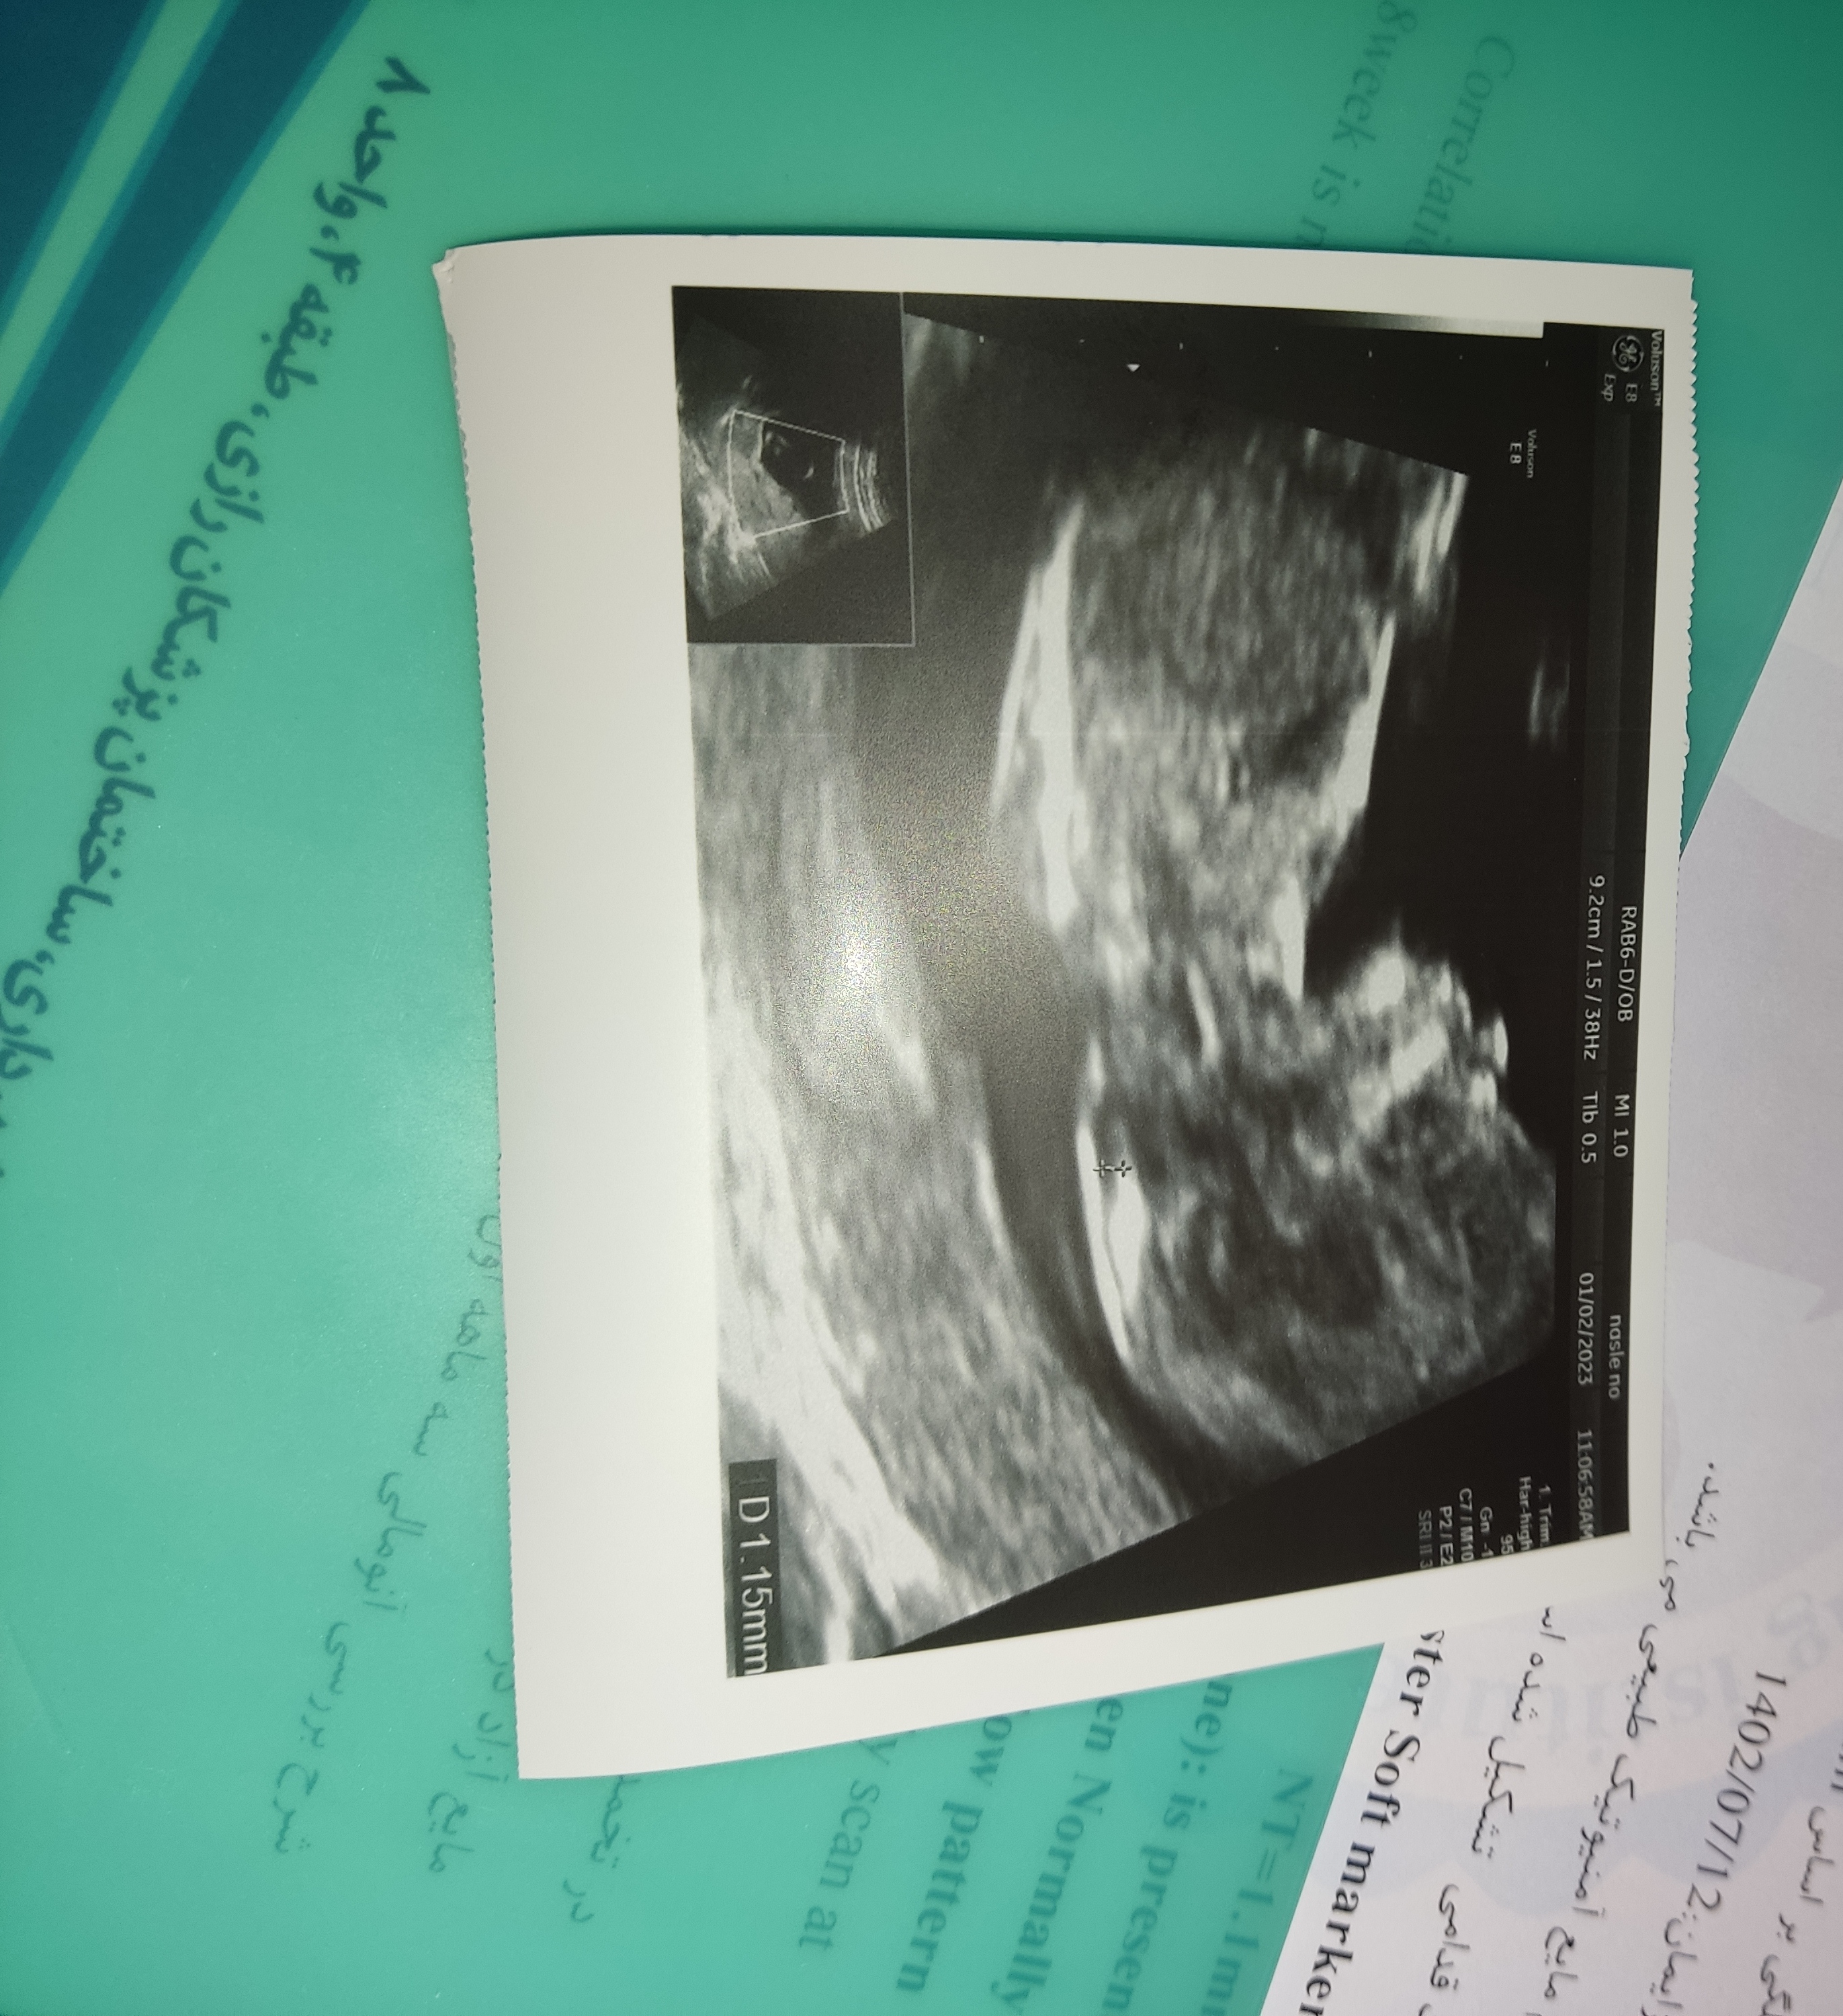

ان تی چی گفت